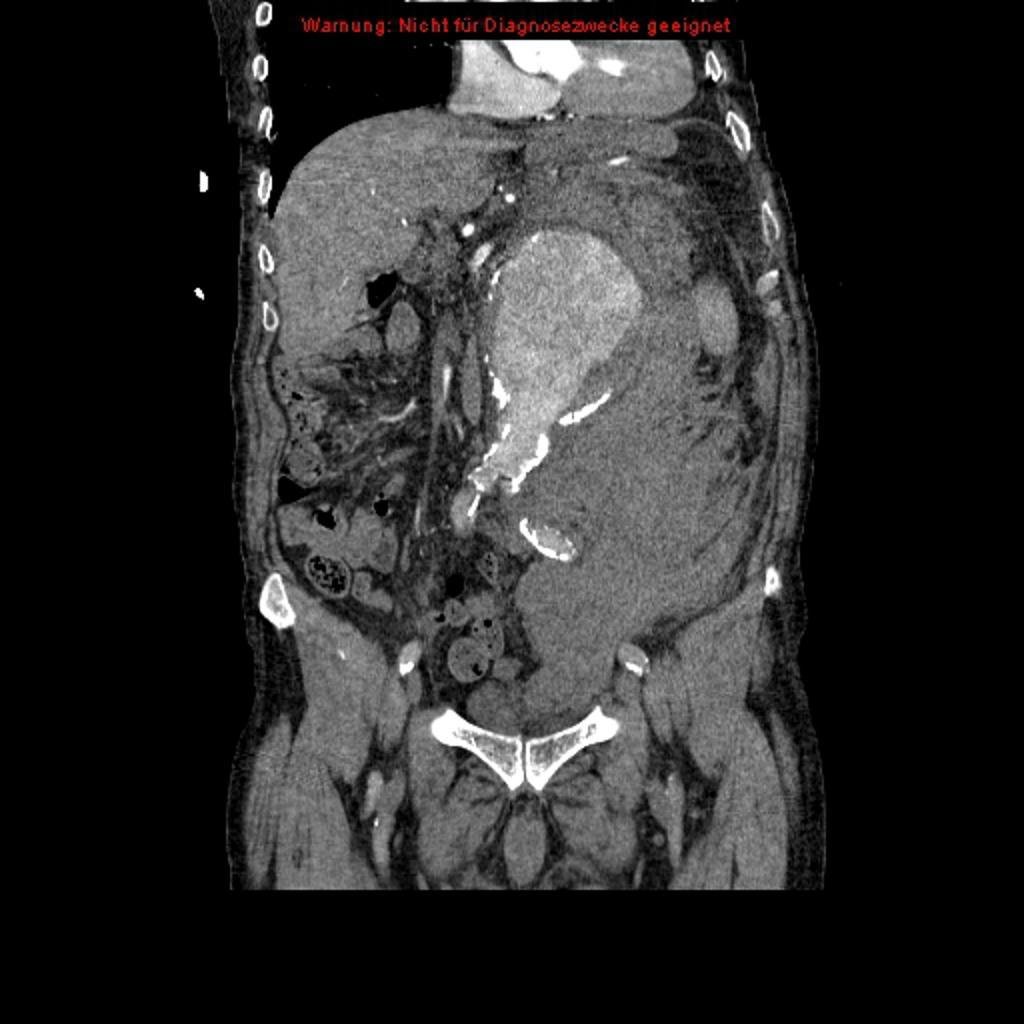

Maligniteit

Wervelmetastasen of leptomeningeale metastasen

Oudere patient met  in prostaatca in VG met pijn in de rug die niet houdingsafhankelijk is en krachtsverlies in beide benen. Daarbij gewichtsverlies en nachtzweten.